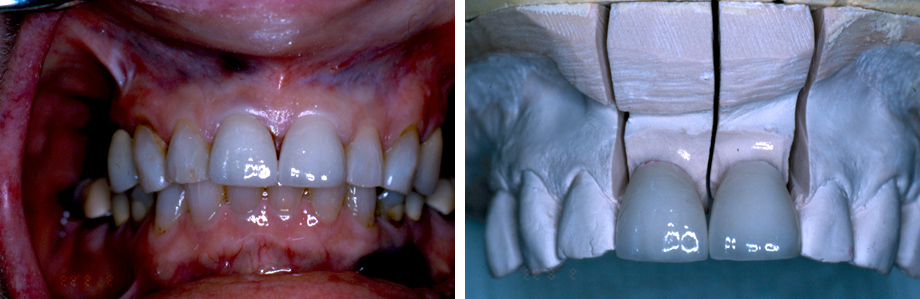

Η διαδικασία ολοκληρώνεται σε δύο επισκέψεις. Στην πρώτη προετοιμάζεται το κάθε δόντι για να δεχθεί την όψη πορσελάνης. Αφαιρείται η δυσχωμία, διορθώνεται το σχήμα και στη συνέχεια λαμβάνεται ένα αποτύπωμα το οποίο αποστέλλεται στο εργαστήριο και κατασκευάζεται το εκμαγείο όμοιο με το στόμα και πάνω σ’ αυτό θα ολοκληρωθεί η όψη πορσελάνης. Μέχρι να είναι έτοιμη αυτή προσαρμόζονται μεταβατικές όψεις από σύνθετη ρητίνη όμοιες με τα διπλανά δόντια. Στο επόμενο ραντεβού γίνεται η οριστική τοποθέτηση των πορσελάνινων όψεων. Συχνά εμφανίζονται αυτά τα μαύρα τρίγωνα. Αιτίες μπορεί να είναι ουλεκτομή και ουλοπλαστική για διόρθωση ουλικού χαμόγελου, θεραπεία περιοδοντίτιδας ή και υφίζηση των ούλων απλά λόγω ηλικίας.